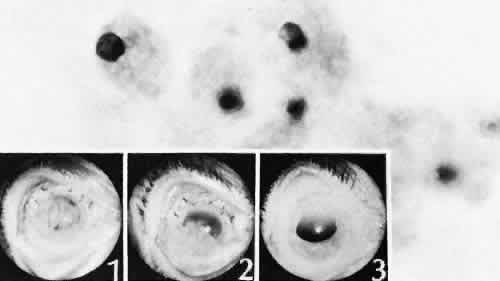

Fig. 41. Two cases of Soemmerring's ring cataract (retained lens cortex and capsule). A. Extensive opaque, well-delineated material is present in a ring-shaped configuration following a partially successful cataract extraction. The opacity is delimited by the remaining lens capsule and is located primarily in the region of the lens equator. B. The eye was examined at autopsy. The reaction is limited to the posterior chamber and within the lens capsule. Surrounding lens zonules and ciliary epithelium are not affected. C. Lens cortical material is retained in the equatorial area of the lens. This area is the least surgically accessible during cataract extraction and contains the tissue most likely to be left behind. This area also contains the cells with the greatest ability to react to trauma by undergoing fibrous metaplasia. The process is identical to anterior subcapsular cataract formation stimulated by anterior chamber inflammation. (Hematoxylin-eosin stain; × 6.) D. Residual lens cortical material ® can be clearly identified entrapped by residual lens capsule. The reaction in the lens may change the adhesive nature of the remaining anterior lens capsule. Posterior anterior synechia may form in these areas. (Hematoxylin-eosin stain; × 16.) E. In another case of retained lens material, the tissue change is less extensive and more translucent, resulting in pearl-like structures (Elschnig's pearls). The process producing this change is the same as the one in Soemmerring's ring formation, but the reaction is less extensive. Pearls are formed by aberrant attempts by lens cells to form new lens fibers. (Hematoxylin-eosin stain; × 69.)